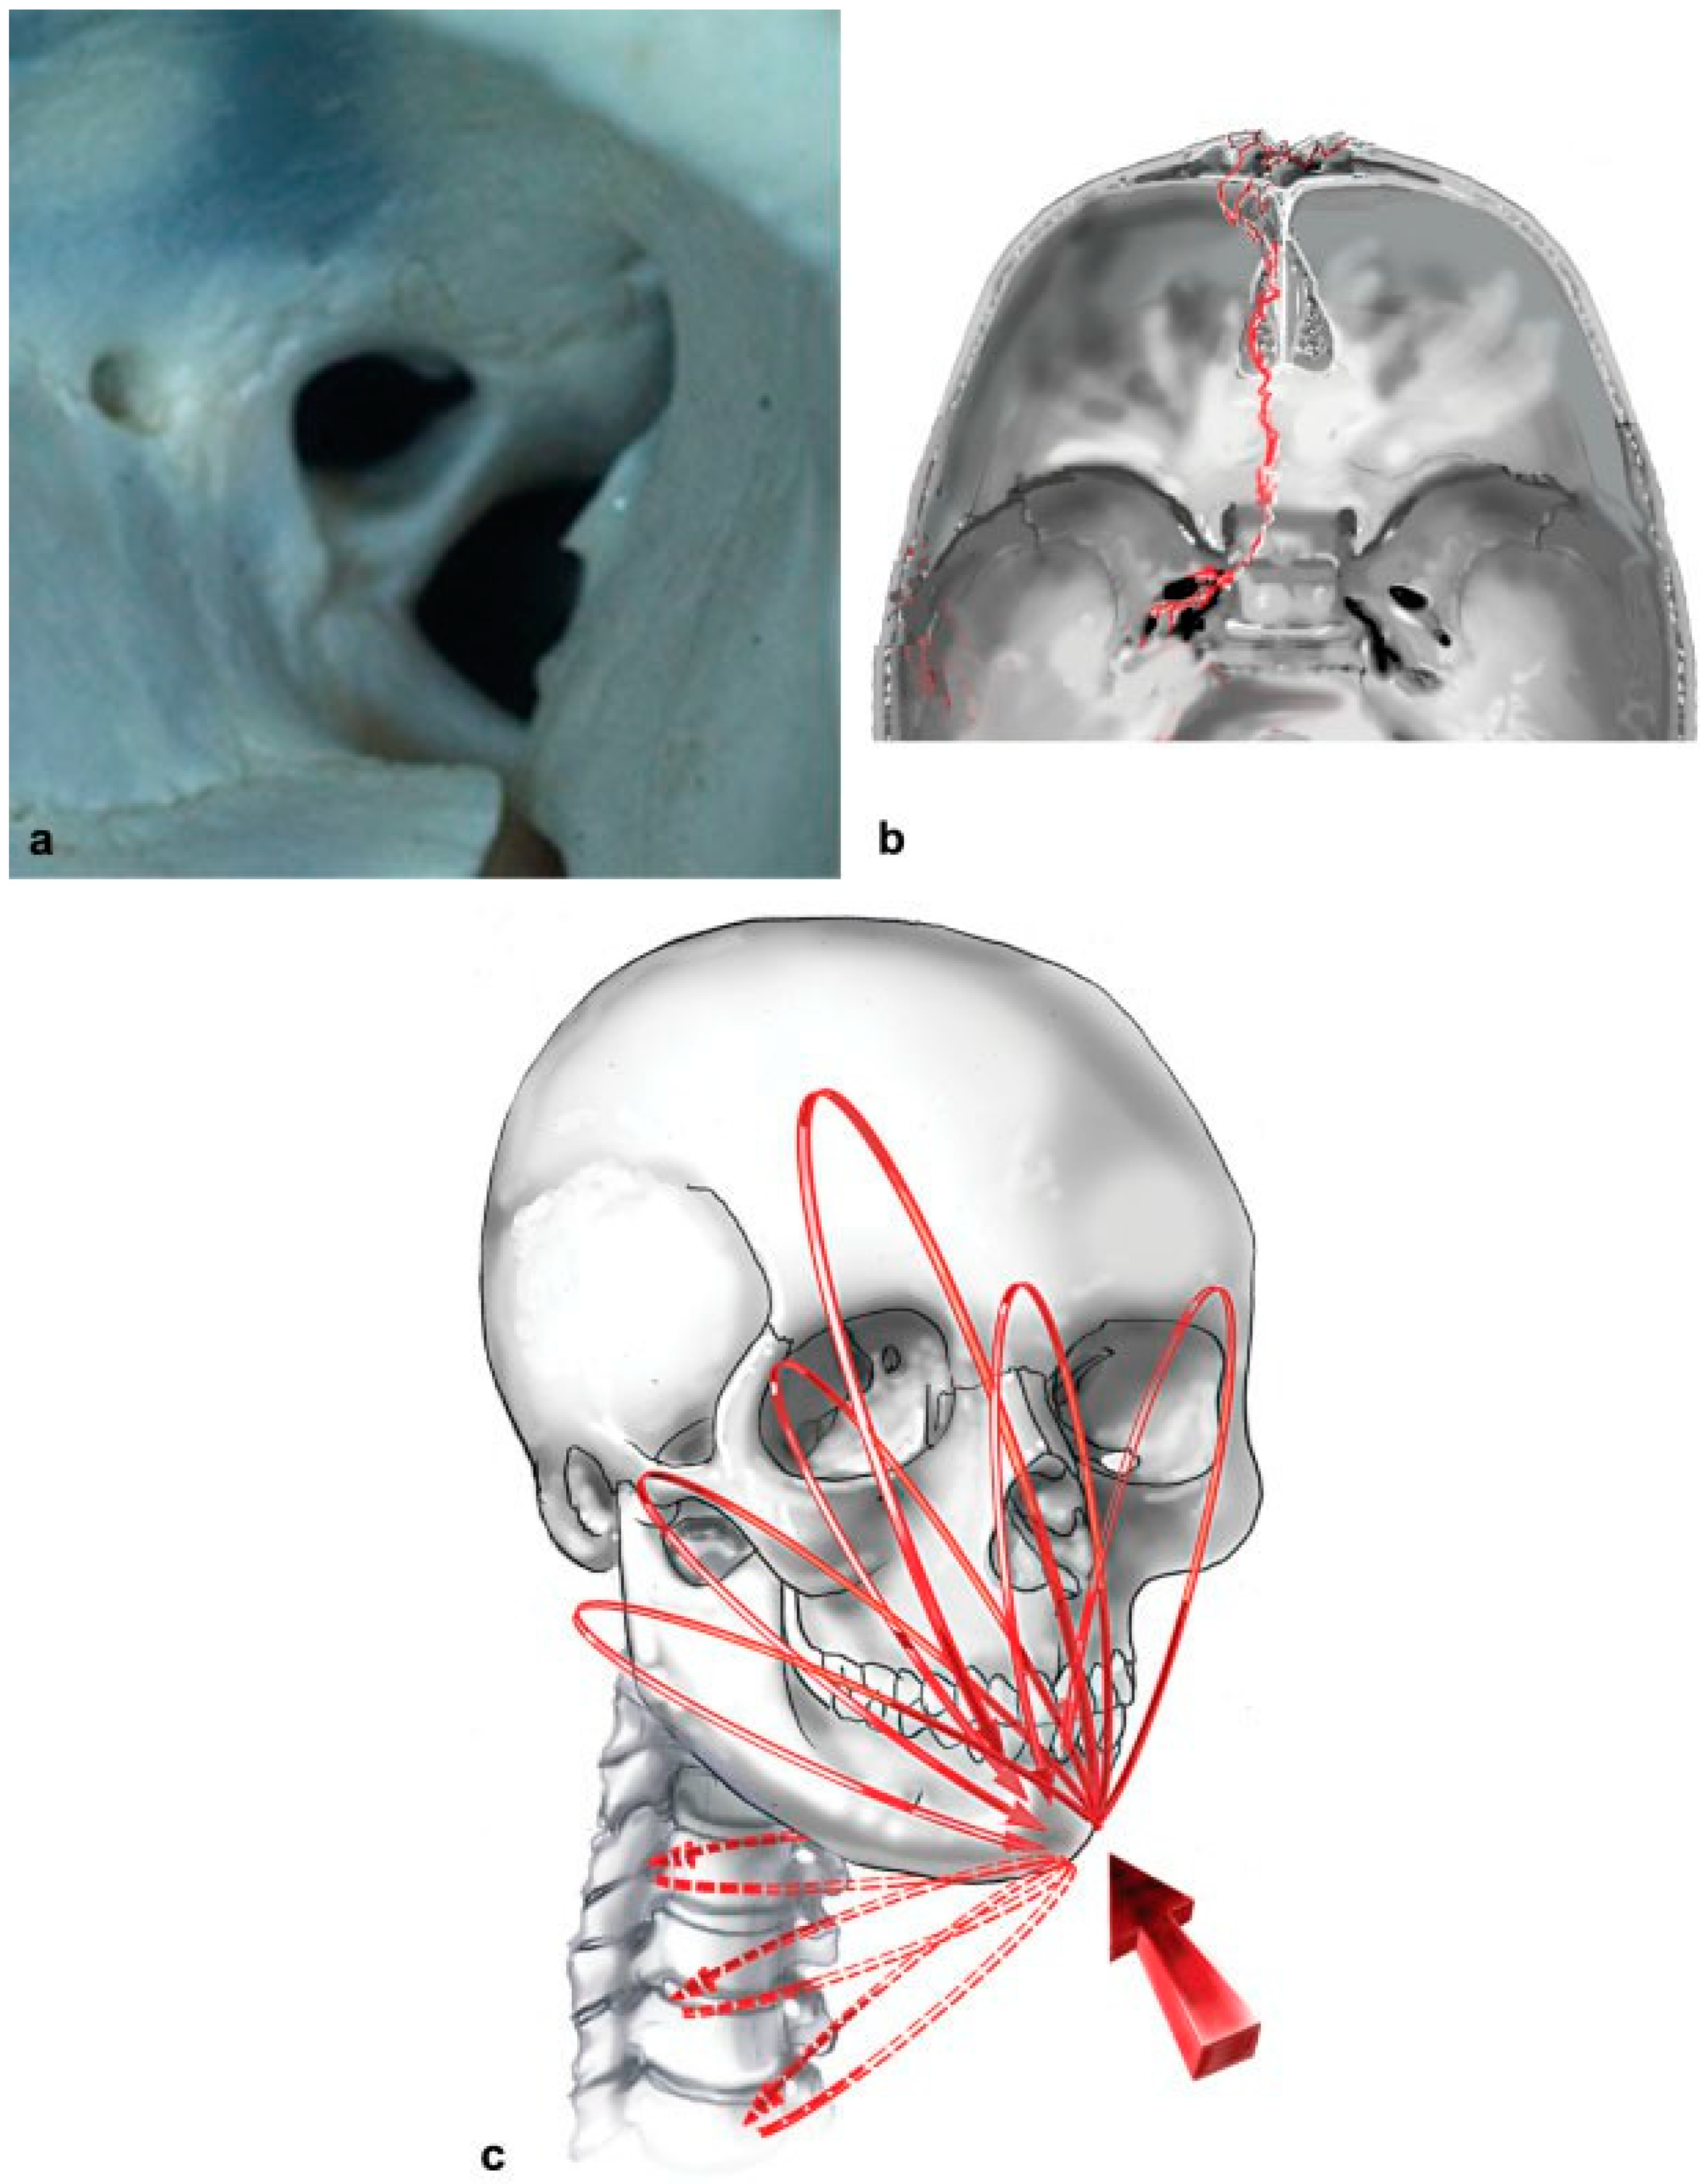

3. “The orbital floor … is formed in greater part by the orbital plate of the maxilla, … and completed anterolaterally by part of the orbital surface of the zygoma and posteriorly by a small triangular area (the processus orbitalis) of the palatine bone.” Whitnall (1921).

The three bones in the floor of the apex are often preserved after high-velocity impact, even when the orbital frame and bilge of the floor of the orbit are disrupted. Preserved apical floor provides structure upon which a split cranial bone graft may rest and is referred to as the “posterior ledge”[34] and the “pre-annular shelf”[33,40] (Figure 19a). Most basilar and frontobasilar fracture lines traverse the roof of the ethmoid, then deviate laterally upon reaching the roof of the sphenoid sinus, to end at the carotid canal or the foramen ovale, lacerum, or spinosum [44] (Figure 19b). Even with such extreme skullbase injury,[43,45,46,47,48] the pre-annular shelf (in the floor of the apex) skirts injury and is consistently available (in a survivor cohort) [48] as a stable platform to facilitate pan-orbital repair.

Figure 19.

(a) The pre-annular shelf in the posterior floor of the orbit is most often preserved despite high-impact injury; the shelf varies in size and bone density and is the key for pan-orbital repair, photograph copyright Richard A. Pollock and Thieme Medical Publishers, Inc. (b) Art depicting the classic location of a frontobasilar fracture skirting the pre-annular shelf of the apical floor to terminate in one of several skull-base foramina, illustrated by Bill Winn, copyright Richard A. Pollock and Thieme Medical Publishers, Inc. (c) Facial force equilibrium circuits (FFEC) according to Rudderman, Mullen, and Phillips and speculated extension of circuits to orbital apex, occiput, and vertebrae of the upper cervical spine,26 illustrated by Bill Winn, copyright Randal H. Rudderman, Robert L. Mullen, John H. Phillips and Thieme Medical Publishers, Inc.

Rudderman et al. have demonstrated distribution of facial force equilibrium circuits (FFEC) to and from the cranium[49] and, we have speculated the presence of circuits to and from “the microbuttresses of the apex of the orbit, posterior skull base (occiput), and the vertebrae of the upper cervical spine” following impact (Figure 19c),[50] even though the shelf in the surviving cohort is most often spared fracture, upon frontal impact.